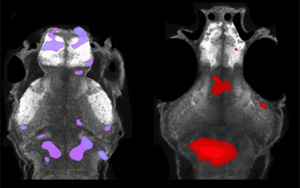

通過由哥倫比亞安蒂奧基亞大學(xué)的研究人員領(lǐng)導(dǎo)的臨床評(píng)估,在Mass Eye and Ear和洛杉磯兒童醫(yī)院進(jìn)行的遺傳和分子研究,在MGH進(jìn)行的神經(jīng)成像和生物標(biāo)志物研究,以及由德國(guó)漢堡-埃本多夫大學(xué)醫(yī)學(xué)中心的研究人員進(jìn)行的神經(jīng)病理學(xué)研究,研究小組確定了一種新的基因變異,可以預(yù)防阿爾茨海默病。該變異發(fā)生在與2019年報(bào)道的同一家族病例不同的基因上,但指出了一種共同的疾病途徑。他們的發(fā)現(xiàn)還指出了大腦的一個(gè)區(qū)域,這個(gè)區(qū)域可能在未來提供最佳的治療目標(biāo)。